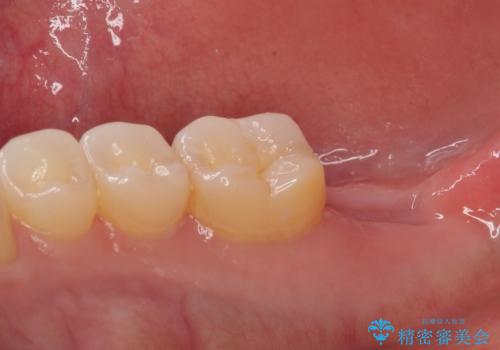

抜歯された骨の穴は、インプラント埋入時にはまだ大きな窩洞となっていましたが、径の大きいワイドインプラントを選択することで、埋入時に十分な安定を獲得することができました。

後方には欠損が残っていたため、補填材を填入しました。

術後にインプラントが骨から脱落することがありますが、特筆するトラブルなどなく、最短の3ヶ月で治療を終えることができました。